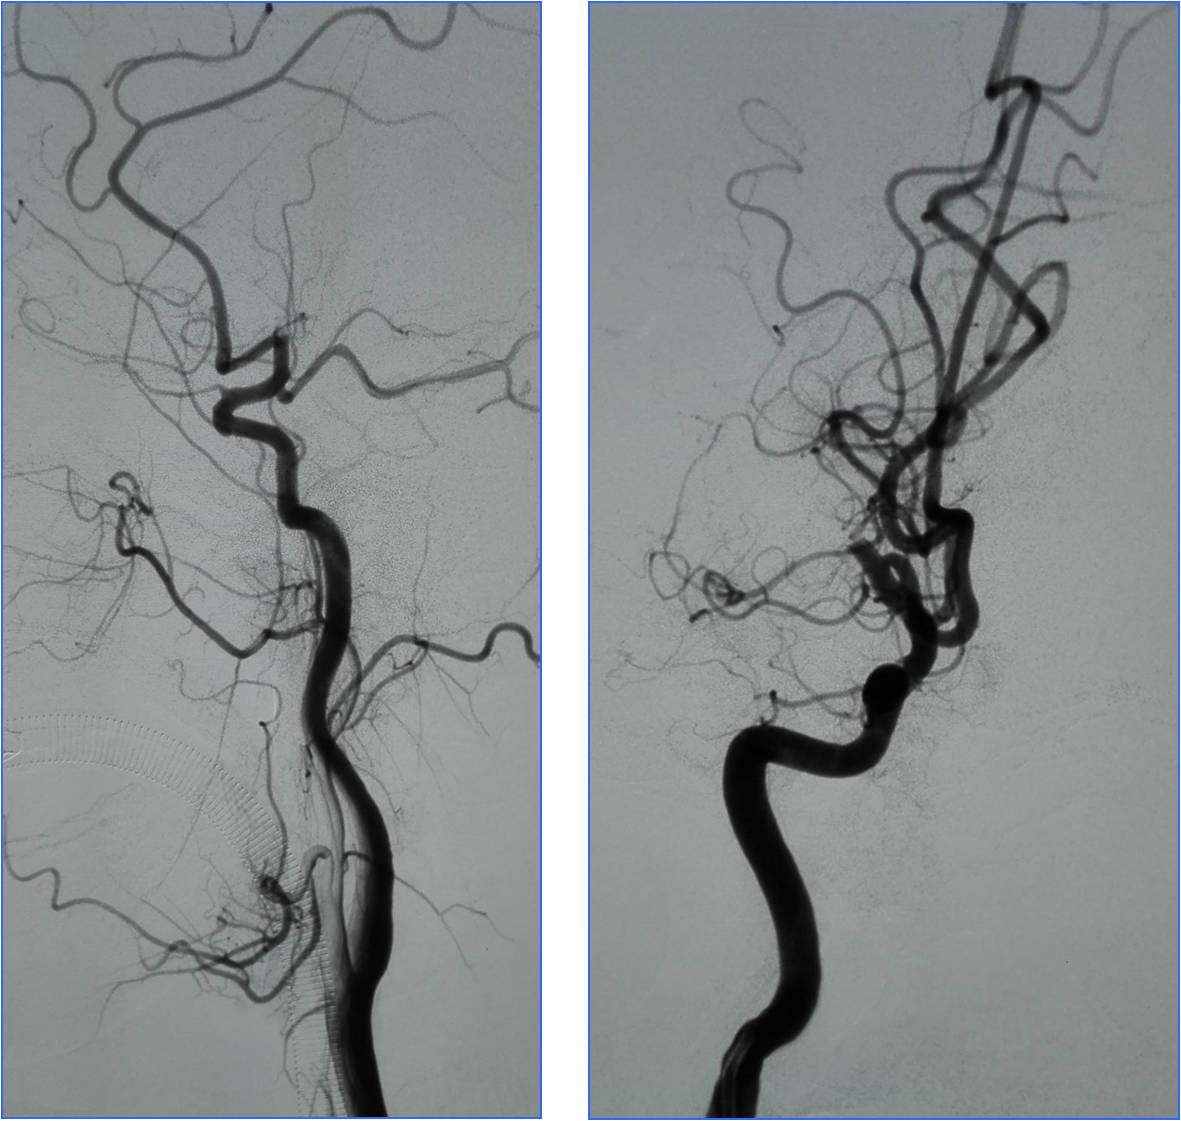

Case2 ICA起始部支架置入

》男,56岁。既往有高血压病及吸烟史。

》因 “言语不清5小时,加重伴左侧肢体无力1小时”于16:30入院。

》查体:血压150/100mmHg。嗜睡,不完全运动性失语,左侧中枢性面舌瘫,左侧肢体肌力0级,左侧巴氏征阳性。NIHSS评分15分。

》头CT(17:00)示右侧大脑中动脉M1及M2段高密度征。

》急查血常规、凝血四项、肝肾电糖。

》签静脉溶栓治疗知情同意书。

》17:50给予阿替普酶静脉溶栓,5mg静推,余45mg持续泵入。

》18:00家属同意行急诊DSA+血管内治疗。

》18:30股动脉穿刺。

》20:30结束手术,送神经内科ICU,给予丙泊酚泵入镇静(持续24小时),乌拉地尔持续泵入控制血压在110/70mmHg左右。

》48小时后转入普通病房,NIHSS评分4分。

》13天出院, NIHSS评分3分。

▼右侧大脑中动脉高密度征

▼M2段栓子

▼将微导管置于右侧大脑中动脉M1段远端,缓慢注入5mg阿替普酶,5分钟后造影见局部血管再通,远端分支显影良好。

Case3 椎动脉开口支架置入